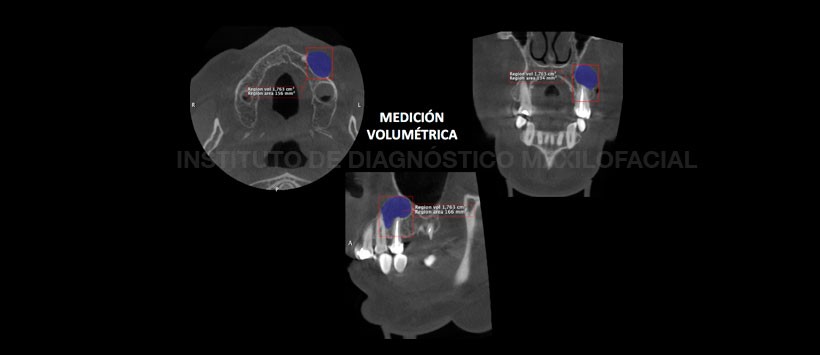

A la evaluación de la tomografía volumétrica (CBCT) en cortes axiales (Figura 2), transaxiales (Figura 3) y tangenciales (Figura 4), se evidencia el proceso osteolítico de límites definidos y bordes parcialmente corticalizados de aproximadamente 1.763 cm3 (Ver figura 5) de volumen que se extiende en sentido caudal-cefálico del tercio apical de piezas 2.3, 2.5 hasta el seno maxilar y en sentido mesio-distal de pieza 2.3 a región del reborde alveolar correspondiente a la pieza 2.6. La lesión ocasiona el desplazamiento del piso y pared anterior del seno maxilar adyacente así como el desplazamiento y erosión de la tabla ósea vestibular.